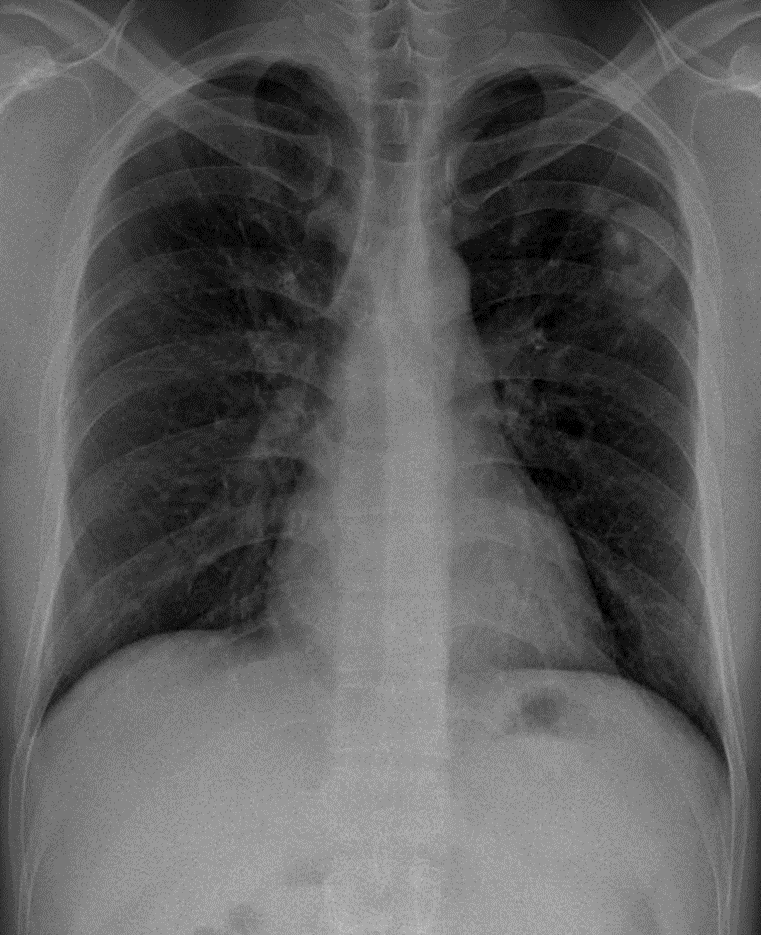

1-U thùy trên phổi (T) 2-Tràn khí màng phổi (T) lượng ít vùng đỉnh